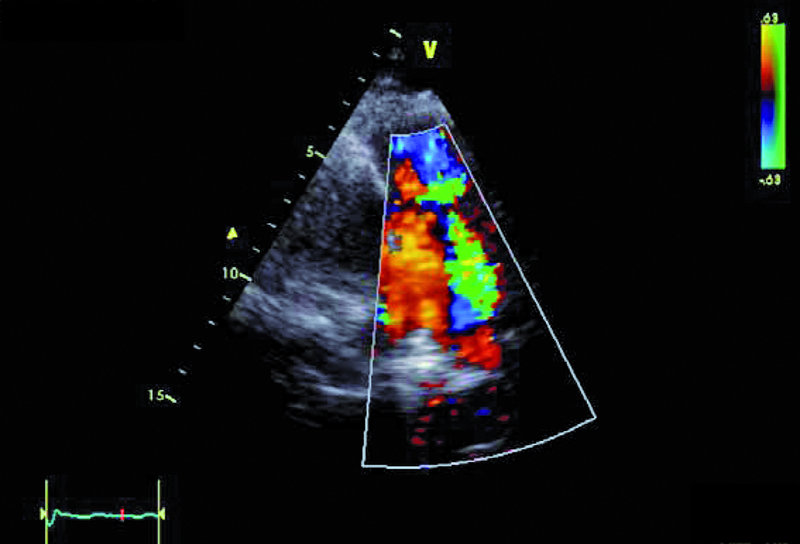

W badaniu echokardiograficznym zwrócono uwagę na powiększenie jamy lewej komory z nieznacznie upośledzoną kurczliwością mięśnia (ryc. 1). Stwierdzono także trójpłatkową zastawkę aortalną (ryc. 2) ze śladową niedomykalnością oraz małą niedomykalność mitralną. Te nieprawidłowości nie mogły tłumaczyć szmeru ciągłego w badaniu fizykalnym ani też nieznacznie powiększonej sylwetki serca. Przyczyną szmeru ciągłego jest najczęściej przetrwały przewód tętniczy Botalla, łączący aortę i pień płucny. Połączenia takiego jednak w miejscu typowym nie znaleziono. Rejestrowano u chorego prawidłową średnicę pnia płucnego (ryc. 3) oraz nieznacznie przyspieszoną prędkość wypływu płucnego (ryc. 4). Szmer ciągły nakazywał poszukiwać innych rzadkich połączeń między dużymi naczyniami. Jedną z nich jest okienko aortalno-płucne, czyli tzw. fenestracja aortalno-płucna, i tę wadę właśnie rozpoznano u chorego.

Okienko powstaje wskutek nieprawidłowego podziału embriologicznego przegrody dzielącej aortę wstępującą oraz pień płucny. Lokalizacja okienka w obrębie aorty wstępującej może być różna, zależnie od tego, która część wspólnej przegrody ulega w toku rozwoju embriologicznego uszkodzeniu – proksymalna czy dystalna w stosunku do zastawek półksiężycowatych. Do rozpoznania wady wystarczy zwykle badanie echokardiograficzne. Na poziomie zastawek powinno się rejestrować dwa niezależne pierścienie zastawek półksiężycowatych. Istnienie okienka może zwykle sugerować brak echa w ścianie między dużymi tętnicami. W tym jednak przypadku takiej cechy nie stwierdzono. Na możliwość okienka wskazywała turbulencja w badaniu kolorowego doplera w pobliżu pierścieni zastawki aortalnej i płucnej (ryc. 5, 6). W badaniu techniką kolorowego doplera rejestruje się przepływ o dużej prędkości, czasami wyraźnie ze strony lewej ku prawej lub przepływ dwukierunkowy. W różnicowaniu trzeba brać jednak pod uwagę inne nieprawidłowości, jak odejście prawej tętnicy płucnej od aorty wstępującej. Dawniej okienko aortalno-płucne operowano za pomocą łaty z dakronu bądź osierdziowej lub przy niewielkiej komunikacji za pomocą szwu. Obecnie, jeśli nie stwierdza się innych współistniejących nieprawidłowości, bierze się pod uwagę zamknięcie okienka za pomocą okludera i do tego rodzaju zabiegu chory został zakwalifikowany. Średnica okienka (4,5 mm) została ustalona w badaniu tomografii komputerowej.